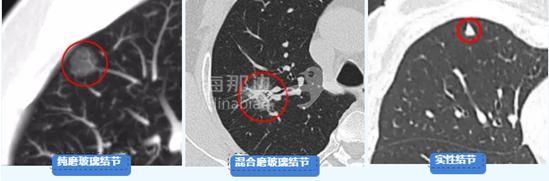

肺部结节按实性成分比例(C/T)分为纯磨玻璃结节,混合磨玻璃结节(部分实性),实性结节。

纯磨玻璃结节:可以是普通炎症、真菌感染、腺瘤样增生、原位腺癌、微浸润或浸润性癌;

混合磨玻璃结节:恶性的几率高,需引起高度重视,特别是实性成分大于50%的结节;

实性结节:虽然恶性概率低,但一旦明确为恶性,相对恶性程度高,进展快,在随访观察中也需提高警惕。

恶性概率:混合磨玻璃结节>磨玻璃结节>实性结节。